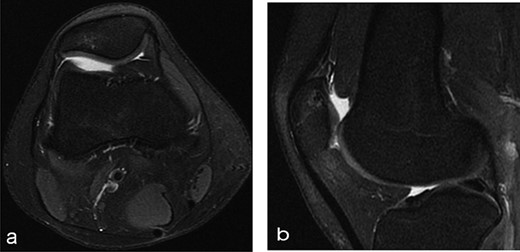

Twelve months after MSC treatment in (a) axial and (b) sagital T2-weighted of MRI T2 sequences the OCD in patella showed that area was almost regenerated with good fibrocartilage morphology.